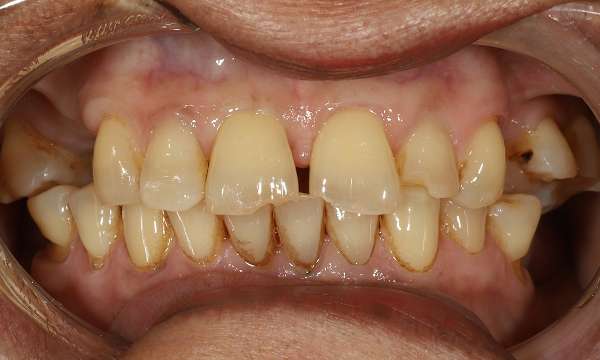

Composite Restorations

This case shows how composite restorations can be used to repair worn front teeth. By conservatively and strategically opening the bite, we were able to create a harmonious and balanced bite, ensuring the newly restored teeth are protected from excessive chewing forces.